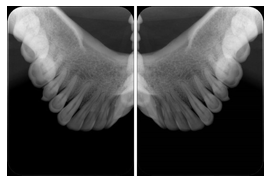

1. A patient in rural Canada visits a general ophthalmologist and is found to have diabetic macular edema. The general ophthalmologist would like to discuss the case with a retina specialist before performing laser surgery. A fluorescein angiogram is done with multiple retinal images taken in a timed series after an intravenous injection. The images along with a Structured Display are shared via a Health Information Exchange with a retina specialist in Calgary, who opens them using his Ophthalmology EMR software and consults via phone with the general ophthalmologist. Both physicians view the images in the same layout so the retina specialist can provide accurate guidance for treating the patient.

2. A patient in rural Iowa visits his primary care physician for management of diabetes. Three non-mydriatic (patient's eyes are not dilated) photographs are taken of the back of each eye, and forwarded electronically along with a Structured Display to an ophthalmologist in Iowa City. The ophthalmologist reads the photos in an agreed upon layout so there is no mistake about what portion of which eye is being viewed. The ophthalmologist is able to tell the primary care physician that his patient does not need to come to Iowa City for face to face ophthalmologic care, but that there is a particular view of the left eye that should be photographed again in 6 months.

Ophthalmic Retinal Study Structured Display

Figure OO-3. Ophthalmic Retinal Study Structured Display